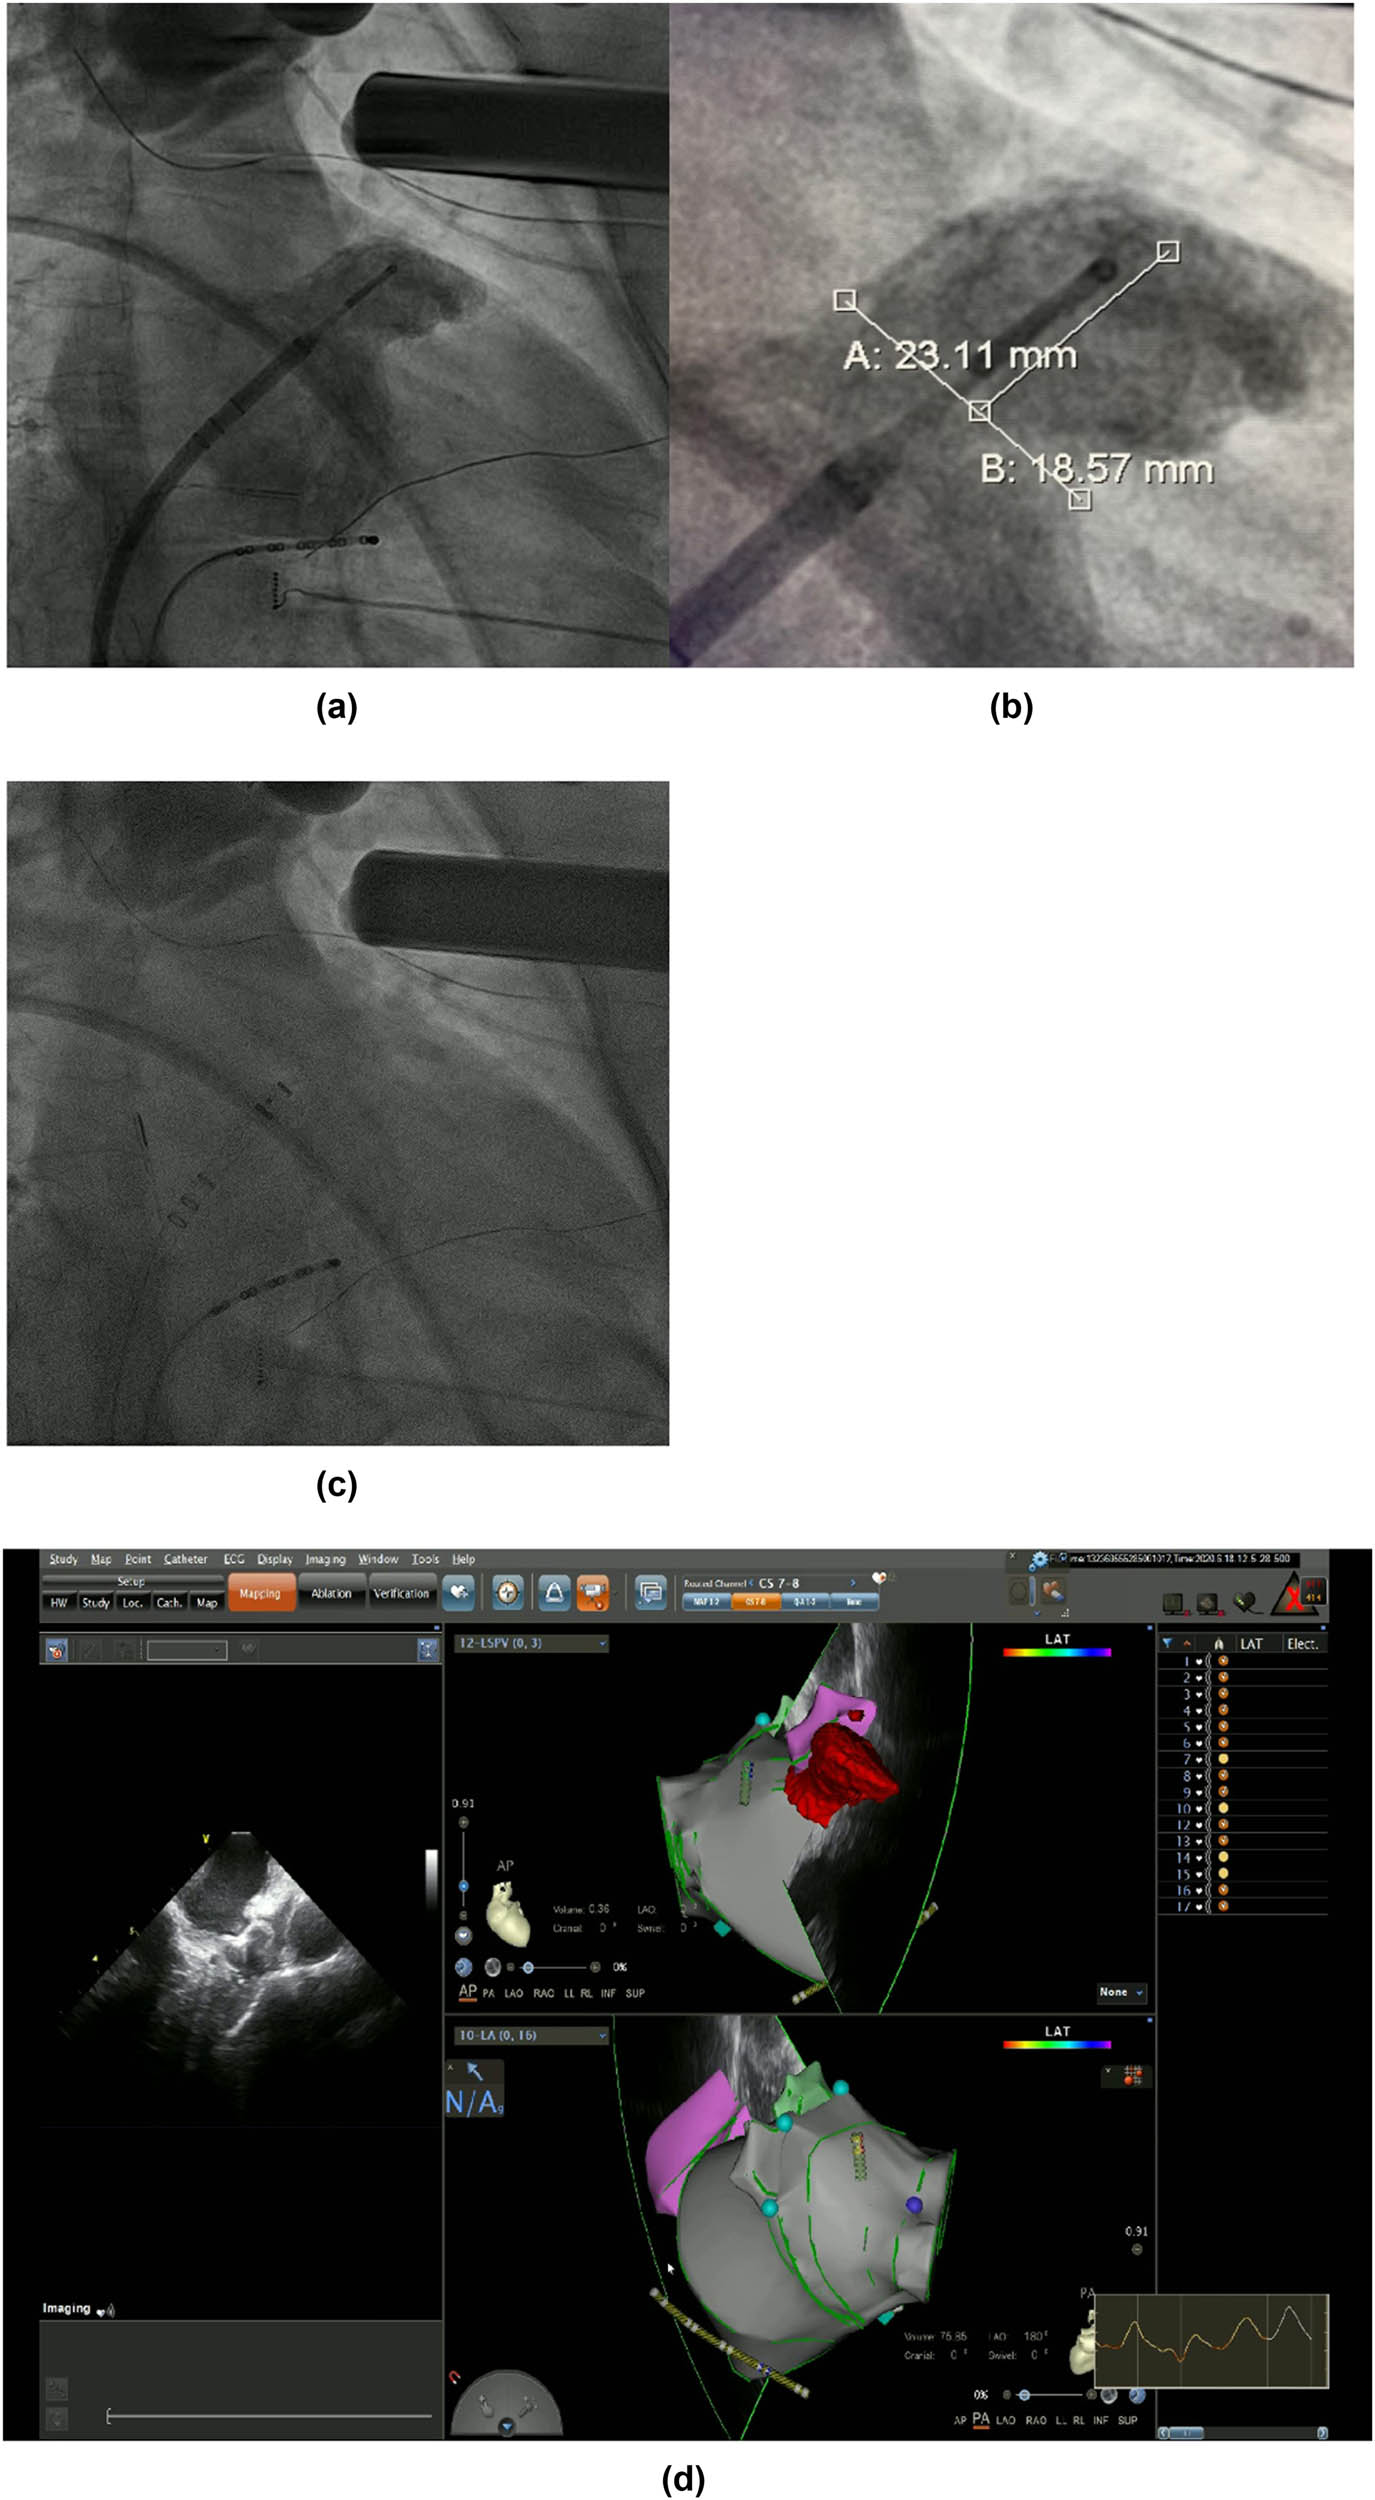

2.4 LAAC procedure

LAAC with WATCHMAN device. (a) and (b) Angiography of the LAA was performed to measure the ostial width and depth. (c) Fluoroscopic view after delivery of the WATCHMAN device in the proper position. (d) Peri-device leakage and compression were detected by TEE post-implantation.